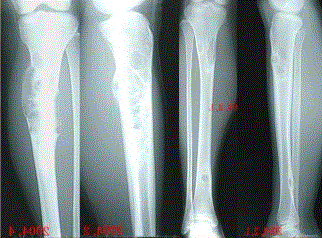

问题 患者女,20岁,右小腿疼痛1周。行双小腿正侧位CR,并行双小腿CT及MR扫描,见下图。 关于病变发生部位,叙述正确的是

选项 A.双侧胫骨干骺端 B.双侧胫骨骨干髓质部 C.双侧胫骨骨干皮质部 D.双侧胫骨骨骺 E.双侧胫骨周围软组织

答案 B